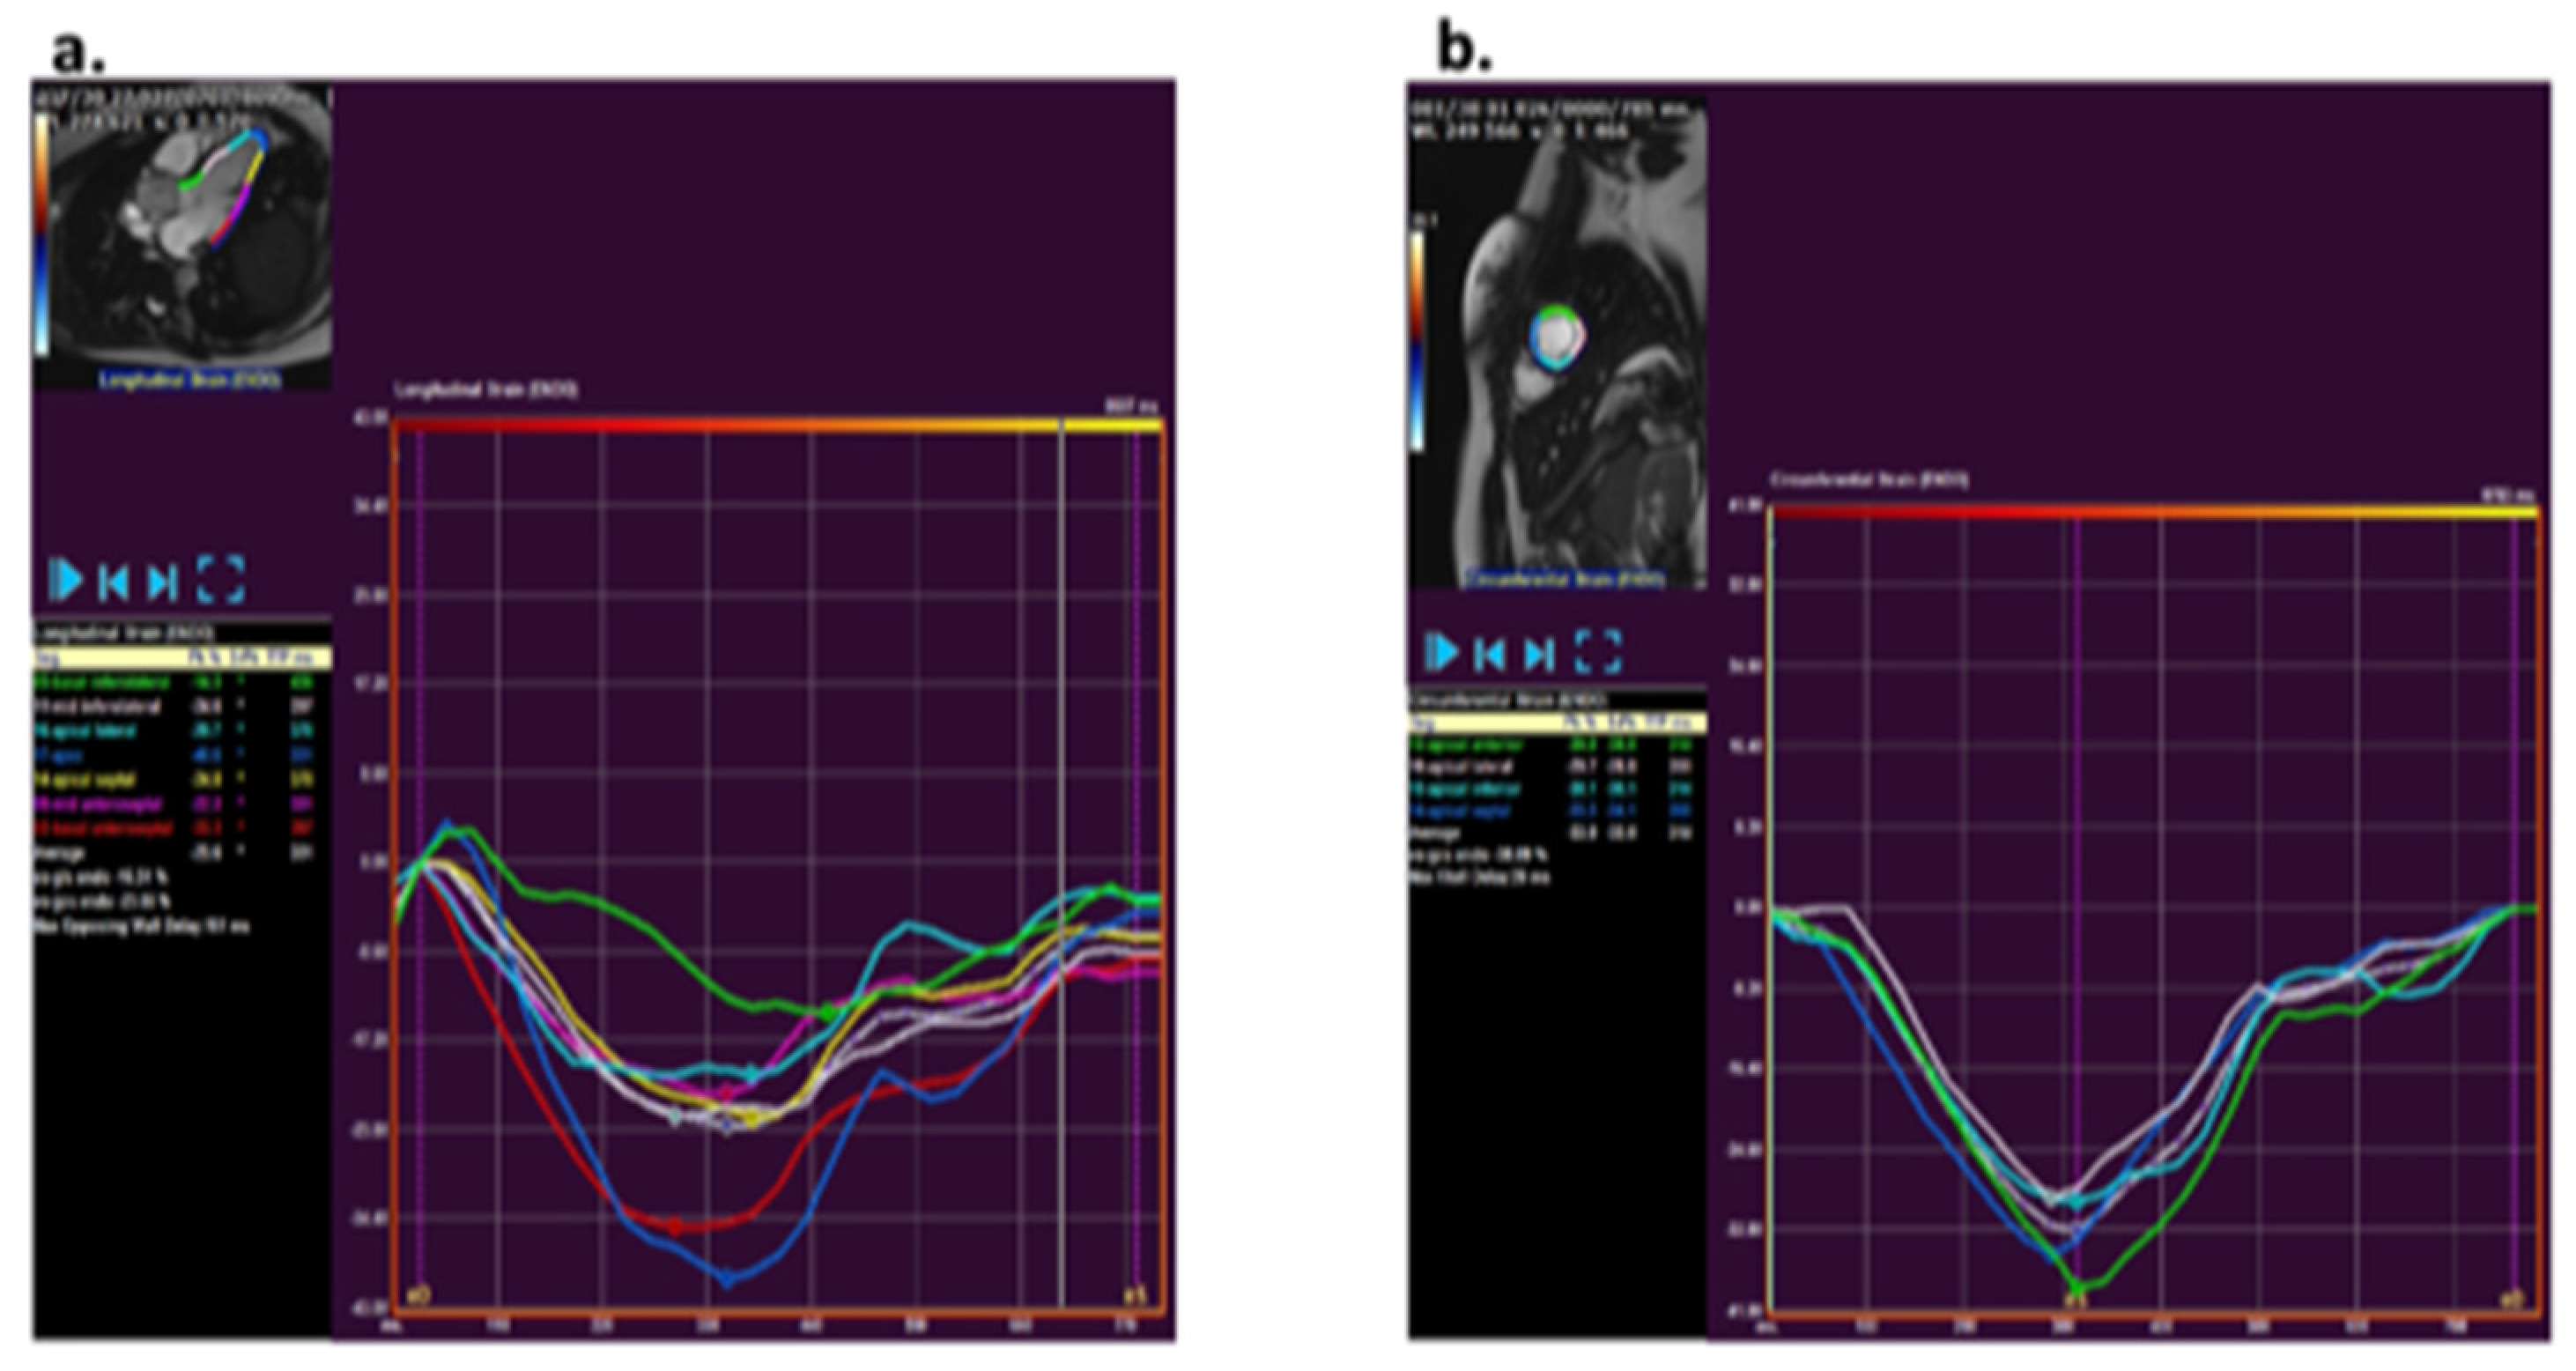

CMR strain analysis was performed by two blinded observers using the feature tracking software QStrain (version 3.1; Medis Medical Imaging Systems, Leiden, The Netherlands). Longitudinal and circumferential strain was assessed by tracing endocardial borders on cine bSSFP images. The longitudinal strain tracing was performed in the two-, three-, and four-chamber views and for circumferential strain in short axis views at the base, mid, and apex (Figure 1). The endocardial borders were manually drawn in end-diastole and end-systole. An American Heart Association (AHA) 16-segment left ventricular (LV) model [12] was used for creating a map of LV longitudinal and circumferential segmental strain and strain rate. Peak strain values and peak systolic and diastolic strain rates were detected and averaged over all LV segments to obtain global peak values.

Figure 1.

Analysis of strain using QStrain (version 3.1; Medis, Leiden, The Netherlands Medis) via a feature tracking method. (a) Example of longitudinal strain post-processing at the three-chamber slice. (b) Example of circumferential strain post-processing at mid-ventricular short axis apical slice.